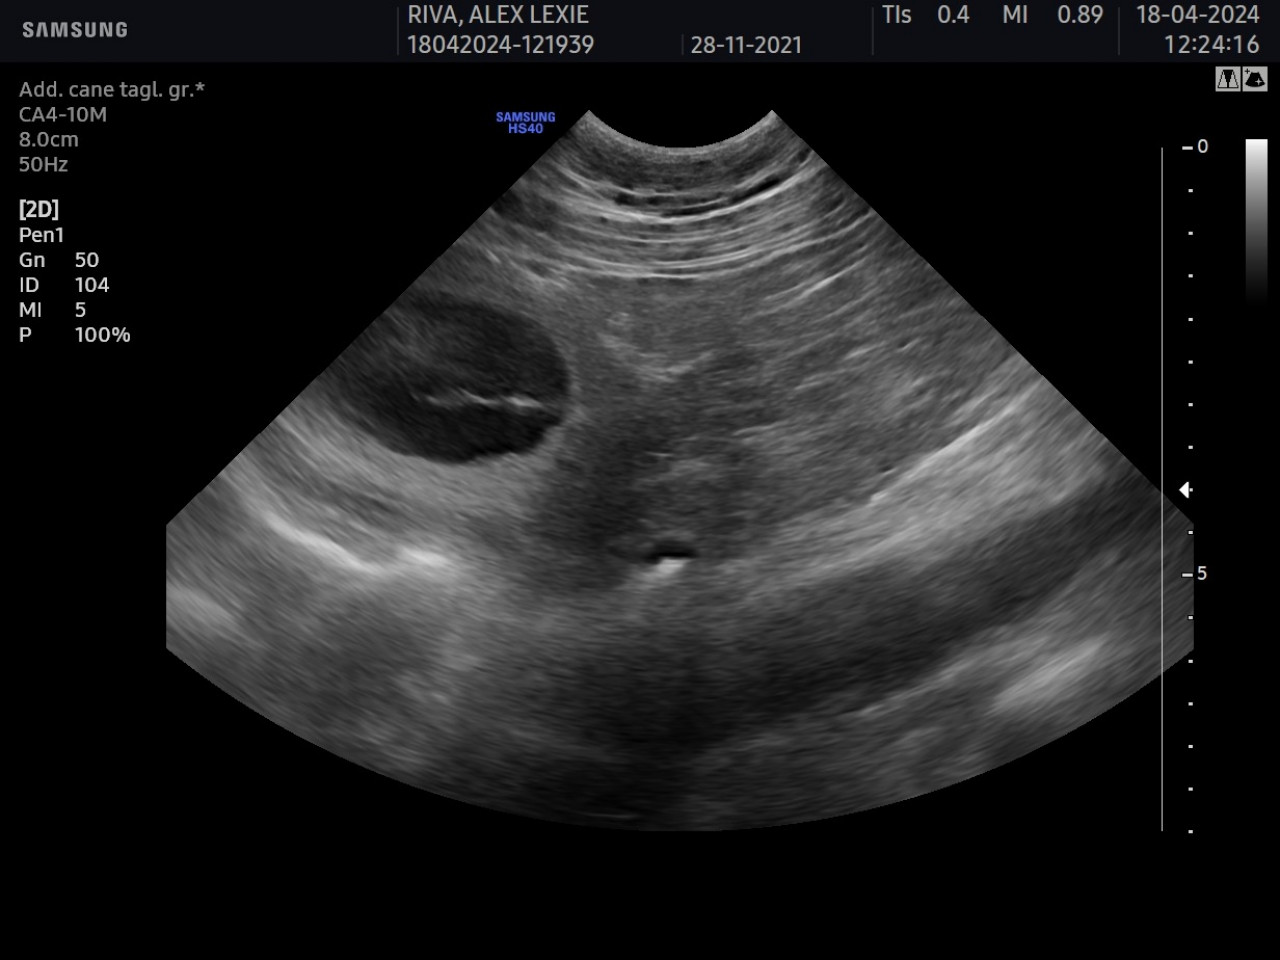

2. Gestation Monitoring

Once fertilization has occurred, the diestrus phase begins. In the event of pregnancy, gestation lasts an average of 63 Β± 1 days from ovulation.